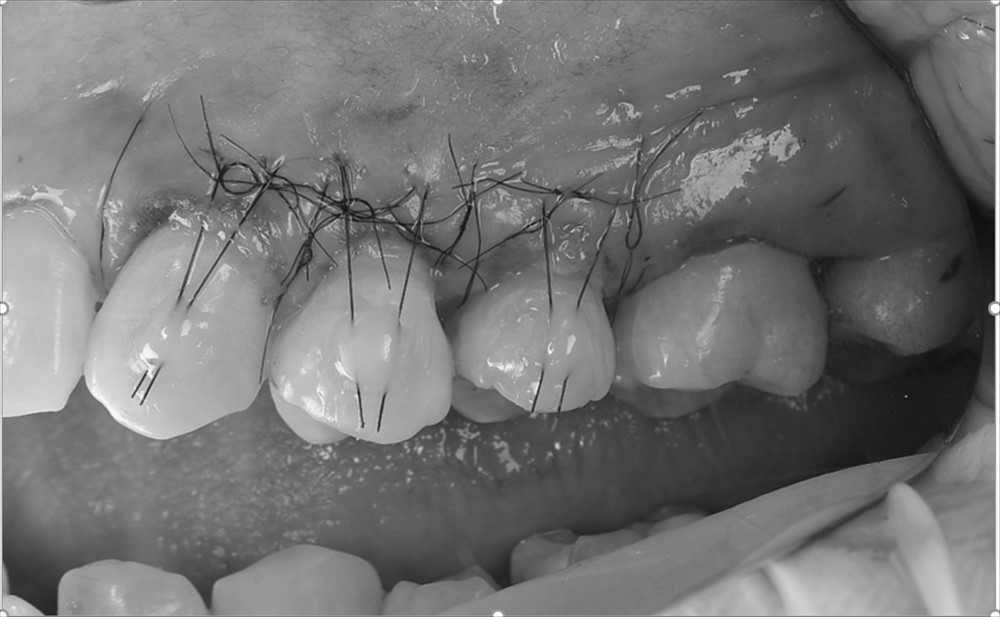

結合組織移植を行い

手術後